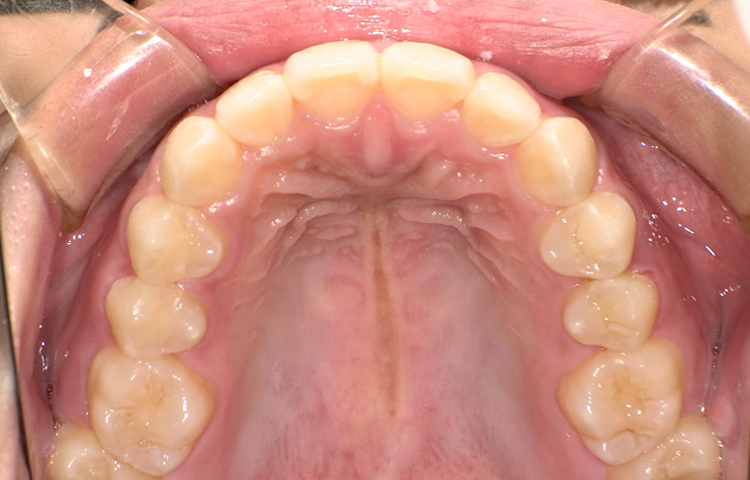

治療後

| 主訴 | 上下の前歯のゆがみ(叢生)を治したい |

|---|---|

| 治療 期間 |

約6ヶ月 |

| 治療費 | 330,000円(税込)/調整費用別途 |

| 治療 内容 |

ワイヤープチ矯正で上下の前歯の矯正治療を行った。 前歯の歯と歯の間をごく少量削り、前歯計8本の向きを揃えた。 見た目が綺麗になったことははもちろん、 磨きにくかったところが磨きやすくなった。 |

| 治療の リスク |

歯と歯の間を削ることでスペースを確保するので、 場合によっては歯が染みる症状が出ることがある。 |